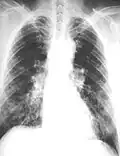

The abnormal chest x-ray and its interpretation remain the most important factors in establishing the presence of pulmonary fibrosis.[11] The findings usually appear as small, irregular parenchymal opacities, primarily in the lung bases. Using the ILO Classification system, "s", "t", and/or "u" opacities predominate. CT or high-resolution CT (HRCT) are more sensitive than plain radiography at detecting pulmonary fibrosis (as well as any underlying pleural changes). More than 50% of people affected with asbestosis develop plaques in the parietal pleura, the space between the chest wall and lungs. Once apparent, the radiographic findings in asbestosis may slowly progress or remain static, even in the absence of further asbestos exposure.[26] Rapid progression suggests an alternative diagnosis.

61-year-old working industrially with asbestos for decades